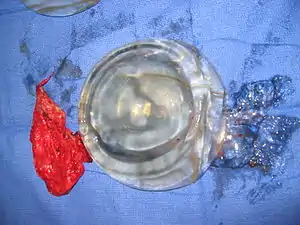

Implant rupture

Because a breast implant is a Class III medical device of limited product-life, the principal rupture-rate factors are its age and design; Nonetheless, a breast implant device can retain its mechanical integrity for decades in a woman's body.[63] When a saline breast implant ruptures, leaks, and empties, it quickly deflates, and thus can be readily explanted (surgically removed). The follow-up report, Natrelle Saline-filled Breast Implants: a Prospective 10-year Study (2009) indicated rupture-deflation rates of 3–5 percent at 3-years post-implantation, and 7–10 percent rupture-deflation rates at 10-years post-implantation.[64] In a study of his 4761 augmentation mammaplasty patients, Eisenberg reported that overfilling saline breast implants 10-13% significantly reduced the rupture-deflation rate to 1.83% at 8-years post-implantation.[65]

When a silicone breast implant ruptures it usually does not deflate, yet the filler gel does leak from it, which can migrate to the implant pocket; therefore, an intracapsular rupture (in-capsule leak) can become an extracapsular rupture (out-of-capsule leak), and each occurrence is resolved by explantation. Although the leaked silicone filler-gel can migrate from the chest tissues to elsewhere in the woman's body, most clinical complications are limited to the breast and armpit areas, usually manifested as granulomas (inflammatory nodules) and axillary lymphadenopathy (enlarged lymph glands in the armpit area).[66][67][68]

When one lumen of a structured implant ruptures, it leaks and empties. The other lumen remain intact and the implant only partially deflates, allowing for ease of explant and replacement.[3]